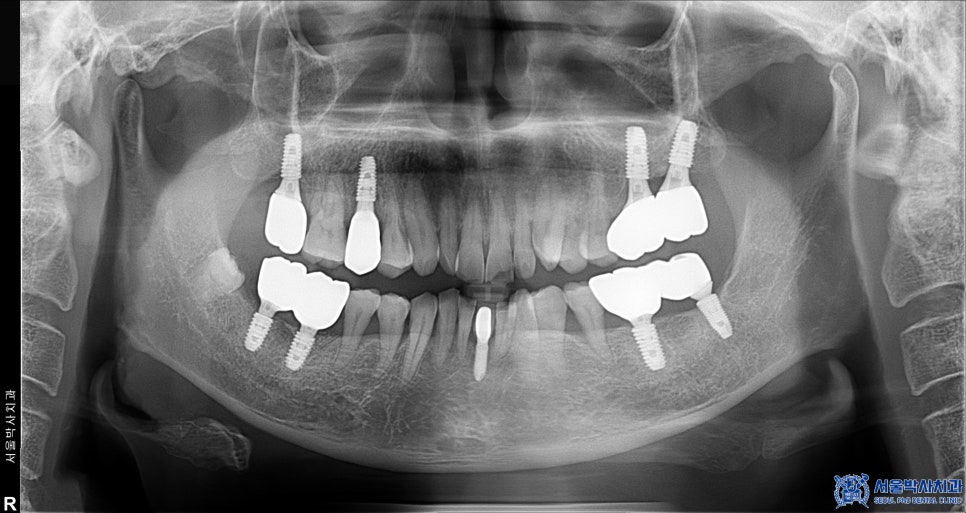

위 환자분은 50대 중반의 남성분으로,

오른쪽 위, 아래 어금니 잇몸이 많이 붓고

흔들림과 통증이 있다고 하셨습니다.

진단 결과, 상악 우측 작은 어금니와

하악 우측 큰 어금니 2개 부위에

만성복합염증이 광범위하게 퍼져 있었고,

염증으로 인해 뼈도 많이

손실된 상태였습니다.

이로 인해 세 치아 모두 흔들림이 심했고,

보존하기 어려운 상태였기에

발치 후 임플란트를 결정하였습니다.